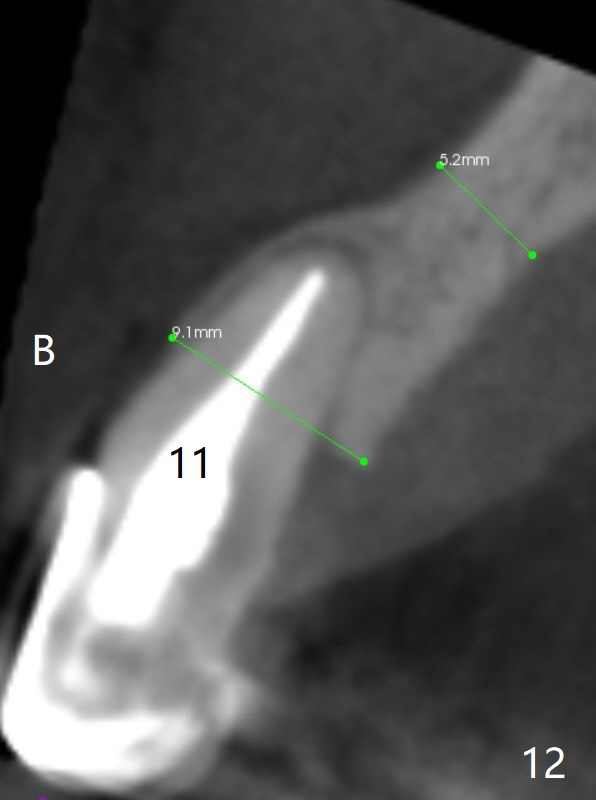

The tooth #10 has severe gingival recession (Fig.1) with loss of the buccal plate (Fig.2 *). After the initial osteotomy depth (Fig.3) increases by 2 mm, a 2.5x14(2) mm 1-piece implant is placed with insertion torque >60 Ncm (Fig.4). Palpation indicates the native bone apparently wider than CT shows. There is no sign of buccal or palatal plate perforation by palpation during osteotomy or implant placement. Vera Graft is placed repeatedly around the coronal threads (Fig.5-7 *). An immediate provisional is fabricated to close the socket (Fig.8). The buccal plate appears to collapse 1 month postop (cortical plate graft apparently more appropriate in this case); the margin of the provisional is trimmed so that the gingiva may grow incisally (Fig.9). The provisional dislodges several times postop due to short abutment. By nearly 4 months postop, the coronal bony defect seems to have been repaired (Fig.10 *). The tooth #11 has tenderness with bone loss (Fig.10 ^), corroborated by CT (distal bone loss, Fig.11 *). Since the apical bone is narrow (Fig.12), a narrow long implant is expected (Fig.13). Use an implant (3.5x13 mm) consistent with those at #14 and 15.